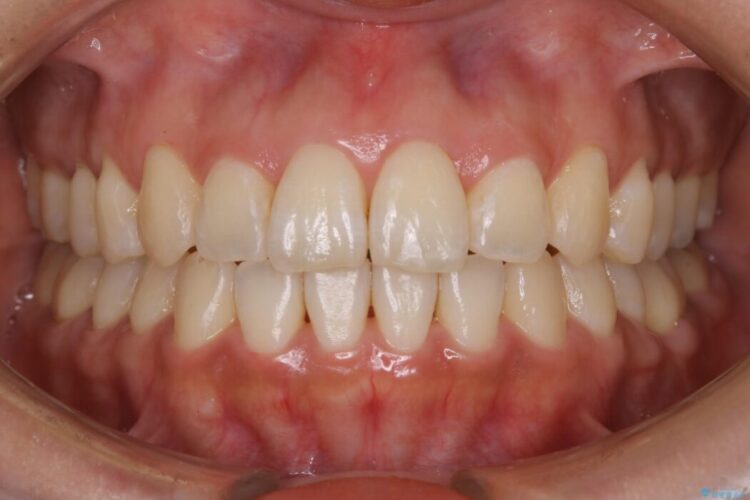

開咬により上下の噛み合わせが悪く、歯列の凸凹も合わせて治療したいとのことで来院されました。

治療後について

きちんと装着時間を守っていただいたこともあり、きれいな歯並びを獲得できました。